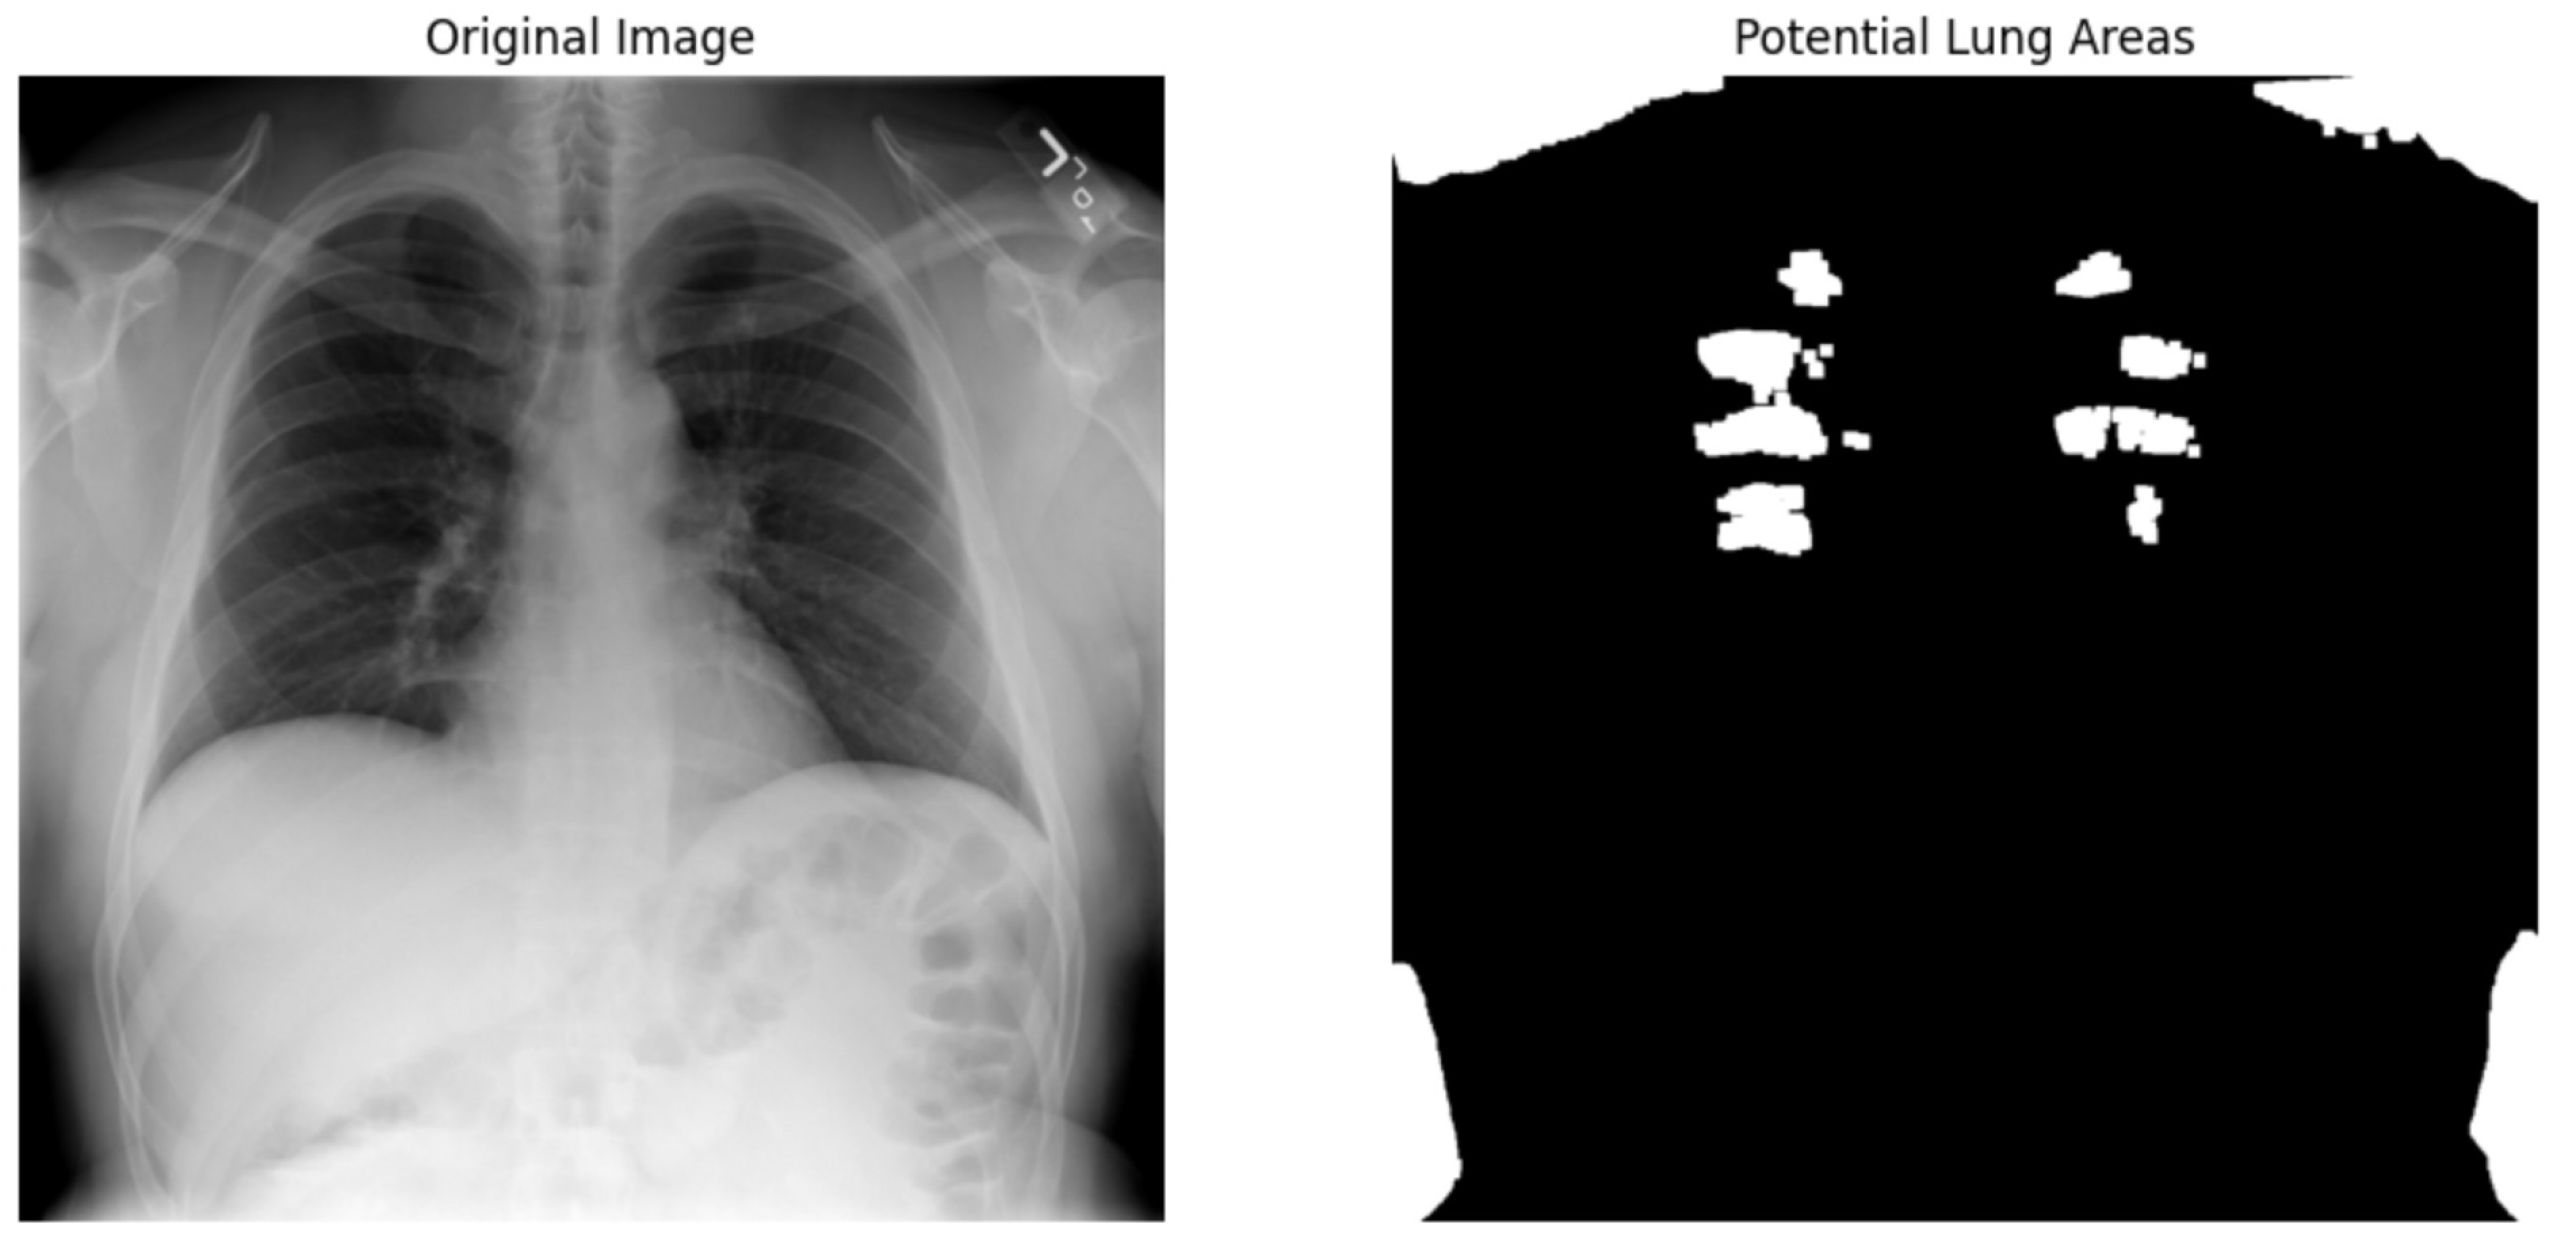

We used the ResNet50 algorithm for feature extraction and compared to other architectures like DenseNet121. Figure 12 ResNet50 employs residual learning with deep residual networks, effectively mitigating the precision of feature maps, which are critical for accurate segmentation and diagnosis in clinical settings. On the other hand, while DenseNet121 is lauded for its feature reuse capabilities and potentially lower model complexity due to fewer parameters, ResNet50’s streamlined data flow and gradient propagation provided a more robust framework for capturing and emphasizing relevant features in chest X-rays. It is crucial for detecting and diagnosing diverse and minute pathological changes within the lungs, offering profound insights into pulmonary conditions in medical imaging. Chest X-ray potential area mark in Figure 13 followed binary thresholding techniques in processing a chest X-ray image to isolate potential lung areas from the surrounding anatomical structures. Binary thresholding is a form of image segmentation that involves converting a grayscale image into a binary image, where each pixel is assigned a value of either 0 or 1 (black or white). The binary thresholding algorithm is particularly effective for enhancing lung tissue visibility against other body components by setting a pixel intensity threshold. Applying such a threshold highlights areas within the lungs that exceed a certain intensity level (shown in white), while less relevant areas remain black. This technique simplifies the image, allowing for clearer identification and analysis of lung regions that could contain pathological features. It aids in detecting anomalies like fluid build-up, masses, or unusual opacities that might indicate conditions such as pneumonia, tuberculosis, or lung cancer. ResNet architecture parameter in Table 8 and Table 9.

We applied scientific analysis on a random 7 sample, which was provided by the clinical specialist. The LIME Analysis for Image Data (a), (b), (c), (d), (e), and (f) is in Figure 22, Figure 23, Figure 24, Figure 25, Figure 26 and Figure 27. There are two parts of LIME analysis from the provided chest X-ray images to detect the disease area. Original Image and LIME explanation;

• Original Image: The patient’s thoracic cavity. It displays the typical anatomical structures of the chest, including the lungs, ribs, and heart.

• LIME Explanation: The result of applying LIME to the chest X-ray image. The yellow boundaries indicate the regions of the image that were most influential in the model’s decision-making process when determining whether the image indicated a particular condition. In this context, these regions are the parts of the X-ray that the AI model considered most important for making its diagnostic prediction.

The analysis very useful for clinicians to understand the model’s behavior and ensure that it aligns with medical expertise. The use of LIME helps in making the AI model’s interpretability decisions more transparent and interpretable. It allows medical professionals to verify whether the AI’s focus areas correspond to clinically significant regions. It also enhanced diagnostic capability of understanding which parts of the images in the AI model in refining the model further and ensures that it makes accurate and reliable predictions. This is particularly crucial in medical diagnostics where interpretability and accuracy are paramount.

Figure 22. LIME Analysis for Image Data (a) on original image to LIME explanation.

Jpm 14 00856 g022